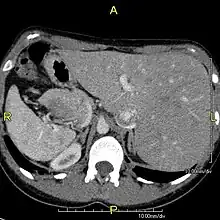

Sagittal CT image showing "tree in bud" appearance of mucous impaction in distal small airways related to primary ciliary dyskinesia

CT image showing dilated and thickened medium-sized airways (bronchiectasis) in a patient with Kartagener syndrome